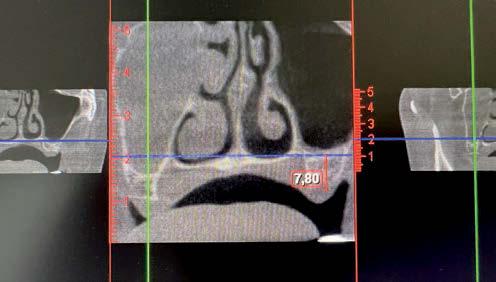

técnicas de abordaje de seno maxilar: elevación convencional o la inserción de implantes cortos y extra-cortos mediante elevación transcrestal, desde enero de 2010 en adelante. Todos los pacientes fueron estudiados antes de la inserción de los implantes mediante modelos diagnósticos, exploración intraoral y realización de un TAC dental (Conebeam) analizado posteriormente mediante un software específico (BTI-Scan II).